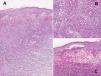

La eco-Doppler del miembro afectado, así como la ecografía abdominal y la radiografía de tórax fueron normales. En la biopsia de uno de los bordes ulcerosos se observó la presencia de un infiltrado inflamatorio, principalmente de neutrófilos, localizado en dermis media y reticular, que estaba edematosa. Existían imágenes focales de vasculitis necrosante junto con exocitosis neutrofílica y pústulas en la epidermis (fig. 2).

Fig. 2.--A) Intenso infiltrado neutrofílico en dermis con extravasación hemática (hematoxilina-eosina, x10); B) vasculitis de algunos vasos (hematoxilina-eosina, x40), y C) pústulas intraepidérmicas (hematoxilina-eosina, x40).